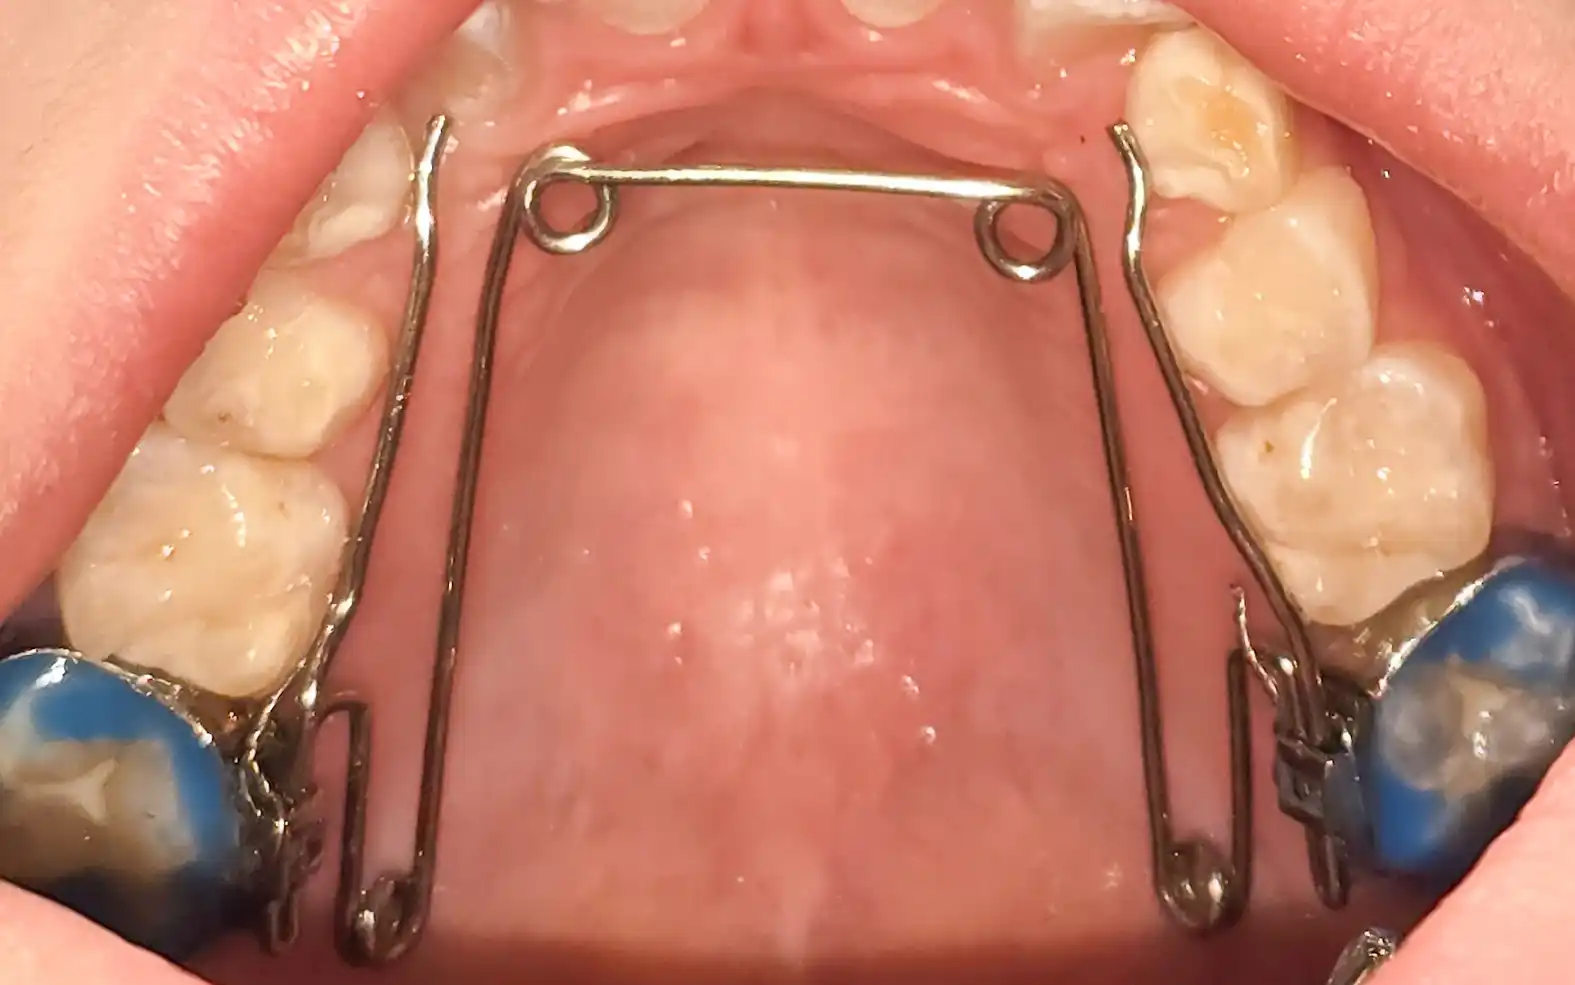

El movimiento dentario no es inmediato ni mecánico. Se basa en la aplicación de fuerzas controladas que permiten desplazar los dientes progresivamente dentro del hueso, generando una adaptación biológica de los tejidos.

Este proceso requiere tiempo, seguimiento y control clínico. No se trata de mover dientes rápido, sino de moverlos bien y esperar que se estabilice lo obtenido y evitar recidivas.

El tipo de aparato utilizado, ya sea brackets o alineadores, es secundario frente a la planificación. Lo determinante es cómo se diseñan los movimientos, cómo se controlan y cómo se integran dentro del objetivo final.